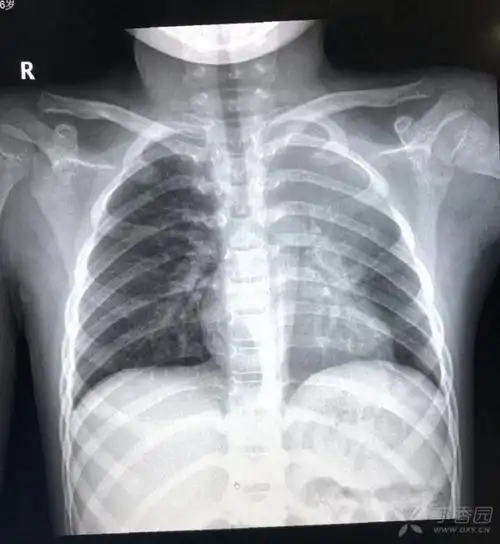

这几组患儿胸片是肺炎还是正常影像规培医师懵了

图片尺寸957x524

胸片可见两肺弥漫炎性渗出影,因此诊断为小儿支气管肺炎

图片尺寸1200x900